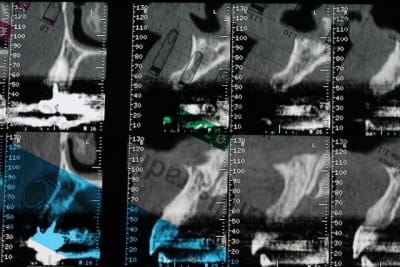

bon, première salve...

photos du scanner...et avec la planche radio pour bien estimer le volume disponible

d'entrée de jeu, on peut se dire que çà va être plus coton pour la 22 que pour la 12 car on à moins d'épaisseur et la corticale est plus dense...